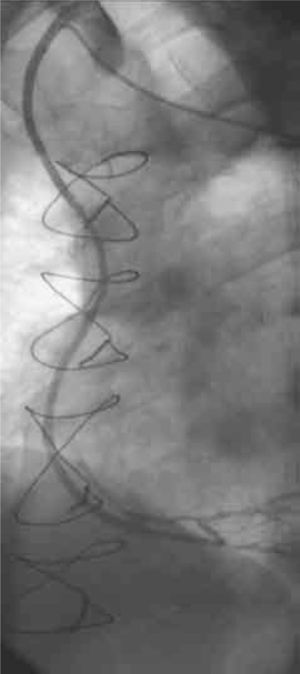

Permeabilidad de los injertosLos seis pacientes se evaluaron a 6 meses de la intervención mediante angiografías de control, constatándose la permeabilidad de todos los injertos realizados (Figs. 1 y 2).

El seguimiento fue clínico y angiográfico. A 6 meses del procedimiento se realizaron estudios angiográficos de control (Fig. 1) en todos los casos, constatándose en ellos la permeabilidad de todos los injertos realizados. A 15 meses (6–31) los pacientes intervenidos quirúrgicamente se encuentran asintomáticos, libres de eventos cardiovasculares, y no han requerido nuevos procedimientos de revascularización miocárdica quirúrgica ni percutánea.